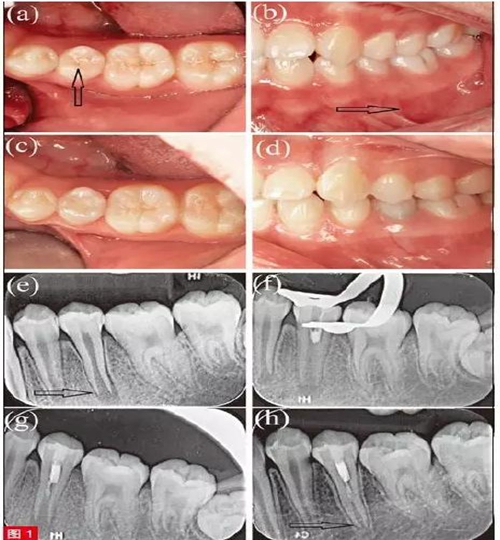

患者為10 歲男童,主訴左下后牙疼痛腫脹2周,6 個月前曾有咬物不適和冷熱刺激敏感癥狀,近兩周出現(xiàn)間斷性持續(xù)自發(fā)痛,且咬合痛明顯加重。病史由患兒本人親訴??趦?nèi)檢查,見左下第二前磨牙(35 牙)牙體變色,面畸形中央尖折斷,未見齲壞(圖1a)。患牙頰側(cè)根尖區(qū)牙齦紅腫,壓痛明顯(圖1b)。冷測和牙髓電活力測試(EPT)示35 無反應(yīng),鄰牙34、36 及對側(cè)同名牙45牙髓活力正常。35叩痛明顯,根尖區(qū)牙齦捫診有壓痛,I 度松動,牙周探診深度為2-3mm。根尖片示35 根尖孔敞開,根尖周大面積透射影(圖1e)。通過臨床和影像學檢查分析,將年輕恒牙35 診斷為有癥狀的根尖周炎。由于根尖孔敞開,牙根尚處于發(fā)育階段,考慮采用牙髓再生治療。分別告知患者及家屬應(yīng)用氫氧化鈣進行根尖誘導(dǎo)成形術(shù)和采用牙髓再生治療的風險、并發(fā)癥、預(yù)后效果?;颊呒覍僮罱K決定采用牙髓再生治療方案,并簽署知情同意書。

首次治療中, 以4% 阿替卡因(Primacaine Adrenaline,法國)局部浸潤麻醉35 牙,橡皮障隔離后,術(shù)區(qū)消毒,高速鎢鋼車針(Diatech,瑞士)開髓。根管不進行機械預(yù)備,20ml 3% 次氯酸鈉溶液(NaOCl)輕柔沖洗3 分鐘,隨后,使用10ml 生理鹽水沖洗3 分鐘。沖洗液中可見黑色碎屑及壞死牙髓組織,此時在根管中段近冠方處可探及連續(xù)成形、仍具有活力的牙髓組織。隨即使用無菌紙尖干燥根管(Dentsply/Herpo,巴西),并待活髓組織表面形成血凝塊。將iRoot BP(Brasseler USA,美國)輕輕置于血凝塊與活髓組織之上(圖1f 和1g),用3M 玻璃離子水門汀(3M ESPE,德國)封閉開髓孔。告之患者及家屬術(shù)后注意事項,保持口腔衛(wèi)生,若發(fā)現(xiàn)任何疼痛腫脹應(yīng)立即復(fù)診。

患者8 個月后復(fù)查,自述經(jīng)部分牙髓切除治療后,自發(fā)痛和牙齦腫脹癥狀逐漸減輕,該牙未再出現(xiàn)明顯不適,偶遇冰水會出現(xiàn)一過性敏感。臨床檢查,35 牙叩診及牙齦根尖區(qū)捫診均無異常,根尖片示35 根尖周組織已完全愈合(圖1c 和1d)。牙周檢查,35 松動度和牙周探診深度均恢復(fù)正常。對35 進行冷測和EPT 測試,顯示牙髓有活力,且EPT 數(shù)值為24,與鄰牙36的EPT 數(shù)值20 相近。根尖片示35 根尖陰影消失,根尖孔有閉合趨勢。